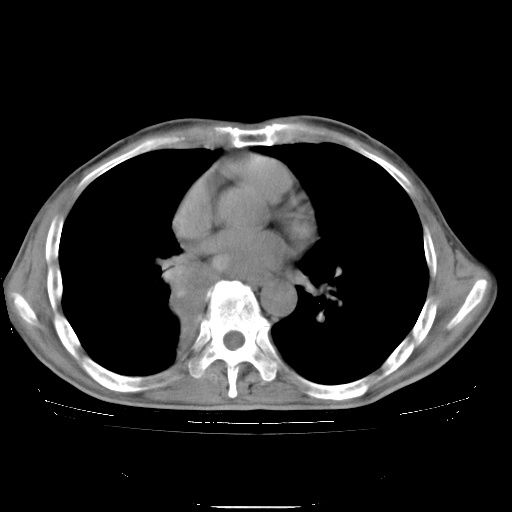

男性患者,63岁。右侧胸背部疼痛2月,加重一周。

考虑:右肺中央型肺癌并右肺下叶不张;两肺尖继发性肺结核。

还有纵隔多处肿大淋巴结及肋骨的改变、两肺多发结节灶。

考虑右中心型肺癌并右下肺不张,肺及纵隔,左肋骨转移。

右肺下叶支气管狭窄闭塞,右下肺不张,气管前间隙淋巴结肿大,两上肺散在分部粟粒灶,沿肺血管支气管束分部,血管支气管束走形较为光滑。考虑右肺中心型肺癌合并肺不张,纵隔淋巴结转移,两上肺癌性淋巴管炎

右肺下叶中心性肺癌并纵隔淋巴结转移,左侧肋骨转移。双肺上叶继发性结核表现。

1)右肺下叶中心性肺癌并纵隔淋巴结转移,两肺转移,左侧肋骨转移。2)双肺上叶继发性结核。

右肺下叶中心性肺癌并纵隔淋巴结及两肺、左侧肋骨转移。双肺上叶继发性结核表现。